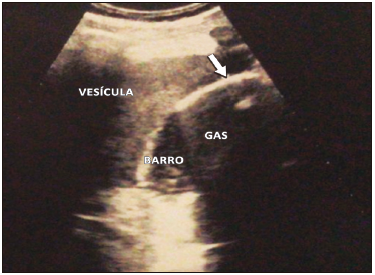

Como primer estudio se realizó una radiografía directa de abdomen. (Figura 3) Se solicitó una ecografía abdominal y una TC de abdomen de urgencia donde se informó la presencia de aire en la pared e interior de la vesícula.

Figura 3. Radiografía directa de abdomen. Se observa imagen radiolúcida (flecha

blanca) en el hipocondrio derecho en topografía de la vesícula biliar relacionada, posiblemente, con

enfisema parietal de dicho órgano, asociado a nivel hidroaéreo. Podría tratarse de un cuadro de CE